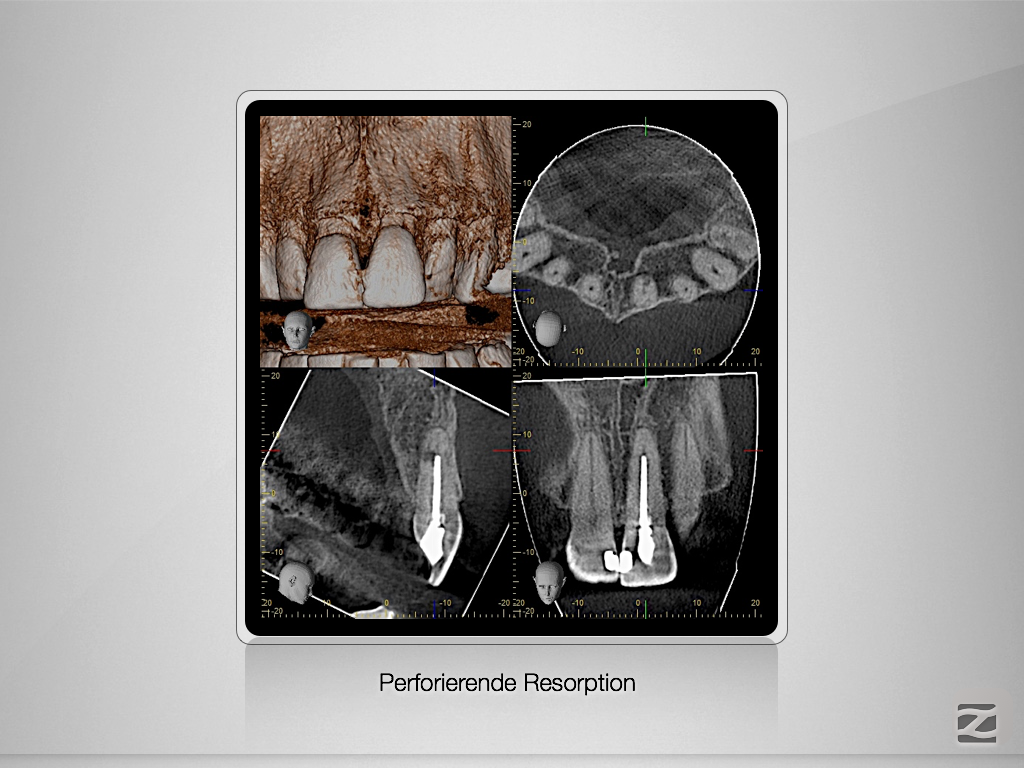

21D.004 Veröffentlicht 21. April 2017 am 1024 × 768 in Perforierende Resorption als Trauma(spät)folge